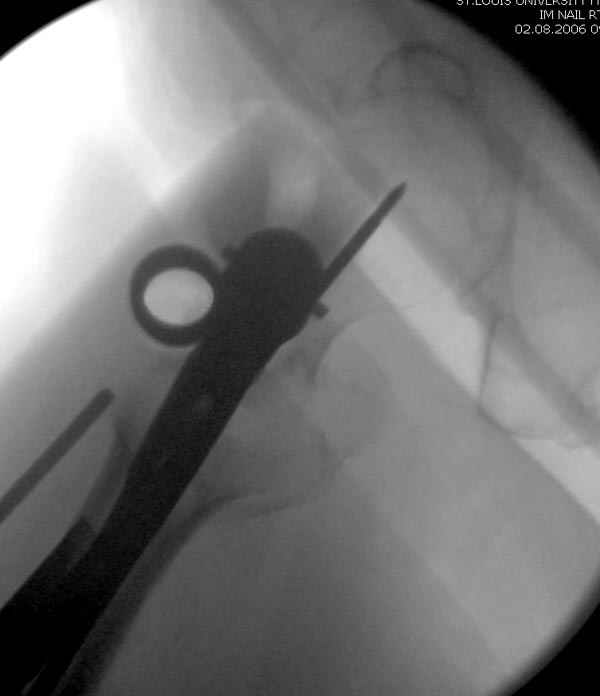

Здесь сканнированные снимки импланта и операционные снимки больной.

На этом снимке процесс компрессии нижним болтом.

Итог